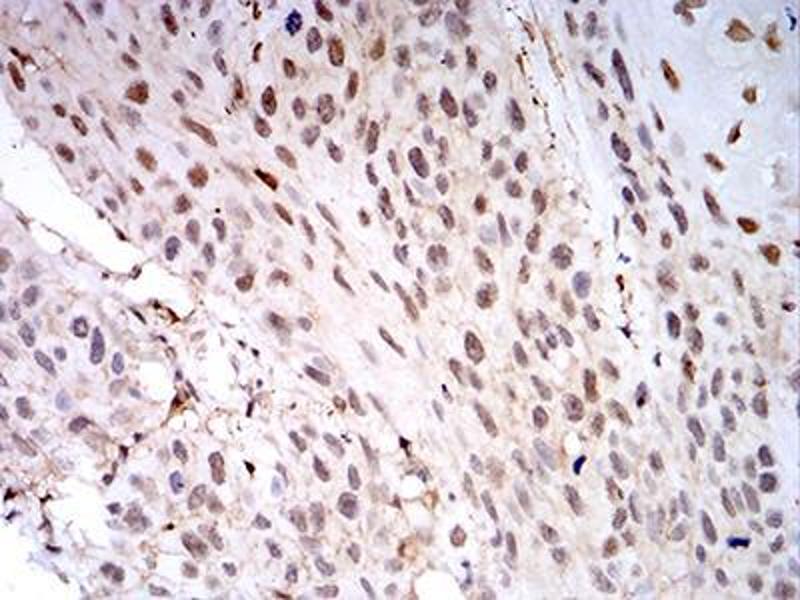

LGALS1/Galectin 1 antibody (AA 1-135)

- Purified recombinant fragment of human LGALS1 (AA: 1-135) expressed in E. Coli.